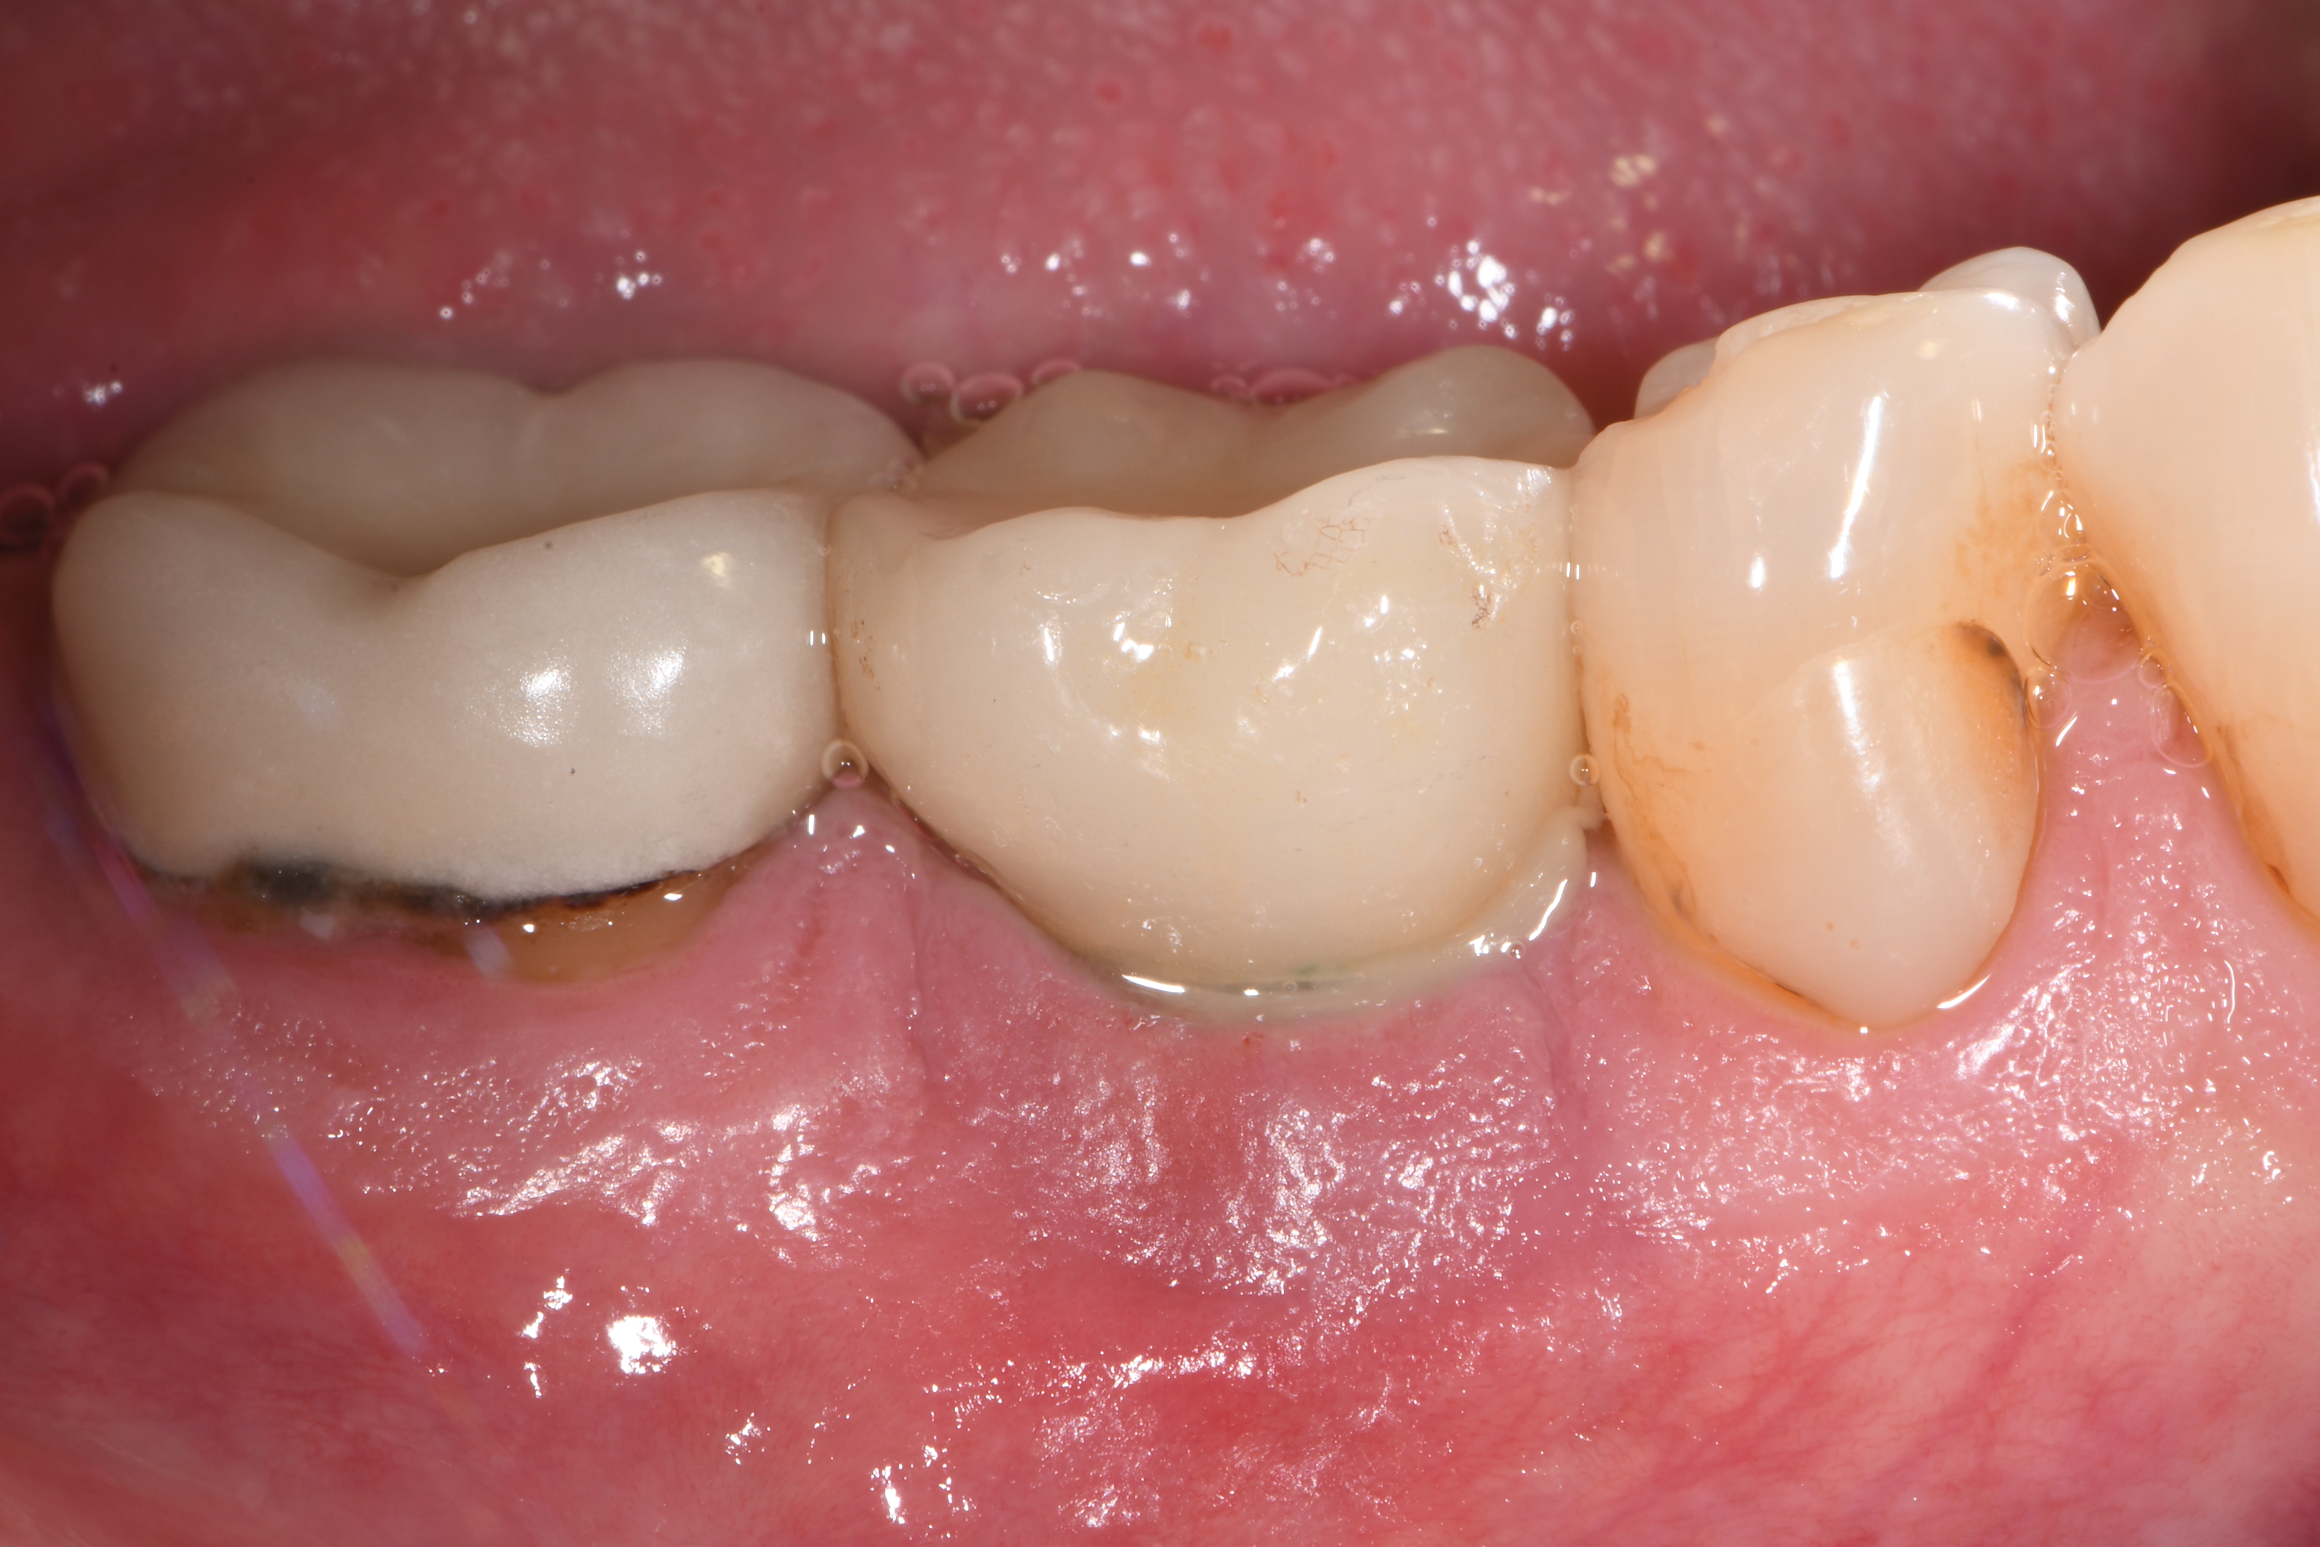

Fig 15. Healing at 10 months postoperative. Although now thinner than preoperatively, the gingival tissue appeared healthier.

Figure 15

At 10 months (Figure 15), it was decided to modify the phenotype by placing acellular dermal matrix (ADM) to increase the soft-tissue thickness. Upon opening of the site, the osseous fill that had occurred in the mesial infrabony aspect could be visualized (Figure 16), and where there was incomplete thread removal at the distal, this area was slightly modified using the implantoplasty burs. The ADM allograft was placed and secured with 5-0 chromic gut suture using an interrupted technique (Figure 17), and the flaps were secured with 5-0 PTFE. At 15 months post-surgery, probing depths ranged up to 4 mm with the absence of bleeding, and the phenotype had been favorably modified (Figure 18).